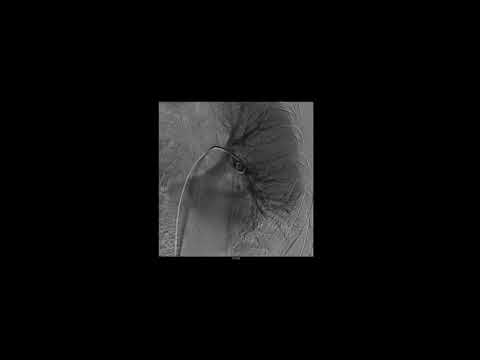

Circulación Pulmonar

Debate abierto - Caso Clínico Dr Martin Bosio Tromboembolismo pulmonar - Caso Clinico - Dr Felipe Julio Chertcoff